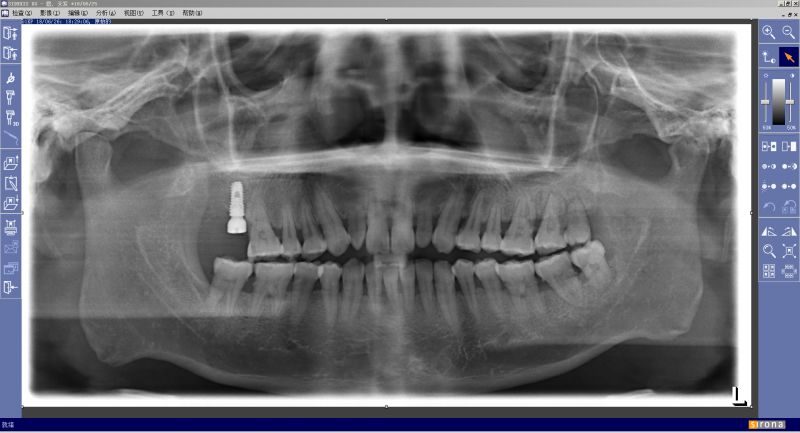

张先生的种牙后牙片(可以清晰的看到一颗种植体)